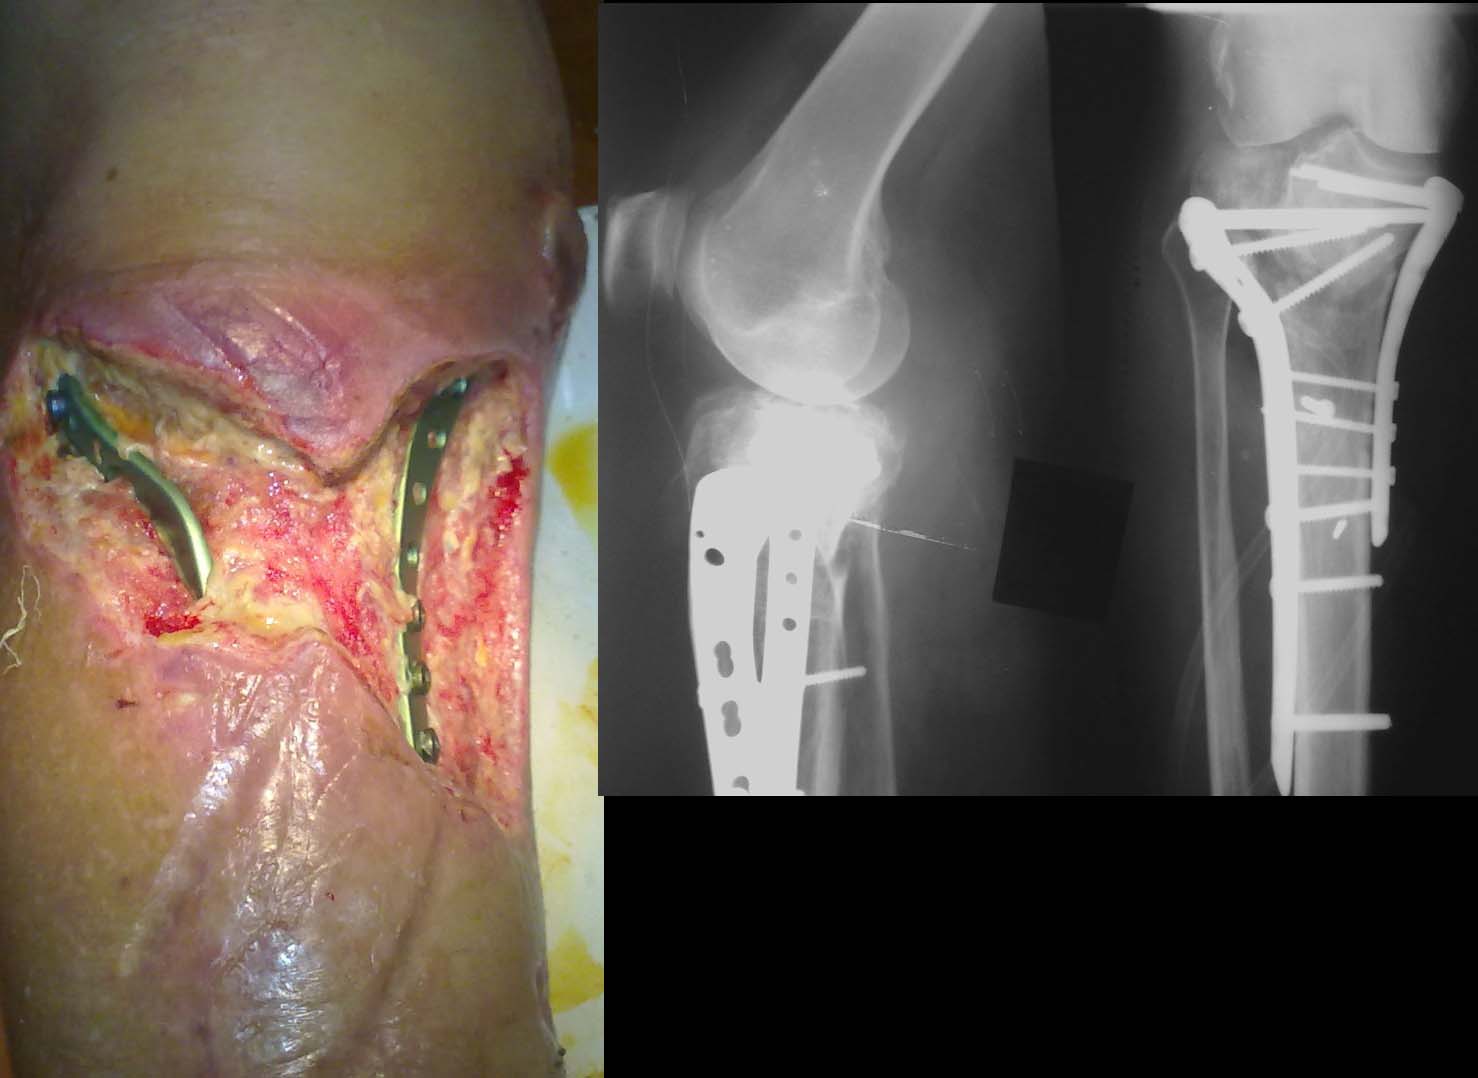

Уважаемые коллеги, прошу поделиться опытом лечения подобных пациентов. П-ка К. 57 лет, страдает инсулинозависимым сахарным диабетом в течение 10 лет, оперирована 03 09 12, на данный момент имеется такая картина. Сахара компенсированы, получает системно а.б. препараты по посеву, ГБО. В течение недели, пока ожидали результат посева, использовали NPWT, сустав пока не пунктировали. Возможно ли использование вакуумной повязки, учитывая возбудитель (Klebsiella pneumoniae)? Стоит ли сейчас удалять фиксаторы с заменой на АВФ? Какие еще эффективные мероприятия посоветуете предпринять? Спасибо за участие.

Удалить пластины. Почистить дырки от шурупов тонкими кюретками, иссечь всё нежизнеспособное (не скелетируя кость). На время очистки раны стержневой аппарат (бедро – голень) я бы положил. Некоторые (V. Herpert) считают нецелесообразно использование вакуумной повязки, когда в процесс вовлечена кость. В данном случае я бы ей воспользовался. Если грануляции выполнят всю поверхность раны, тогда пластика расщепленным кожным лоскутом с заменой фиксатора на аппарат Илизарова со встречно-боковой компрессией (на спицах завязать 8-образные петли, т.к. напайки прорежутся). На сегодняшний день перелом развивается по пути несращения (ИМХО). Если останется голая кость – краевая резекция с пластикой брюшком икроножной мышцы. Тогда аппарат Илизарова будет крайне затруднителен.

Первоочередная задача в Вашем случае санация раны и восстановление мягких тканей в зоне перелома. После хирургической обработки раны можно выполнить закрытие лоскутами из медиальной и латеральной головой икроножной мышцы. Из местных мышечных лоскутов на голени- это наиболее надежные и простые лоскуты. Аутодермопластику поверхности лоскутов лучше выполнить сразу, одномоментно. Технический момент: иссекайте плотный апоневроз по передней поверхности лоскутов, чтобы зона перелома контактировала с хоошоваскуляризированной мышечной тканью, а не с плотным, практически бессосудистым апоневрозом. По поводу удаления фиксатора: несмотря на многочисленные сообщения в литературе, что при условии закрытия дефекта мягких тканей фиксатор можно оставить, я не помню случая, когда нам это удалось. Почти все случаи кончались глубоким нагноением в зоне перелома. Наверное, в Вашем случае мы, совместно с травматологами, поступили бы следующим образом: хирургическая обработка раны, удаление пластины, мостовидная фиксация стержневым аппаратом наружной фиксации (3 стержня в дистальный отломок большеберцовой кости, 3 стержня в бедренную кость, пластика дефекта мягких тканей лоскутами из латеральной и медиальной головок икроножной мышцы, аутодермопластика поверхности лоскутов. Далее через несколько недель, если все получиться и рана не нагноиться можно перейти на фиксацию в аппарате Илизарова.

Добрый день. Удалите пластины, сделайте КТ. Ощущение, что внутренний мыщелок секвестрирован. Временная фиксация наружным аппаратом.Всего доброго.